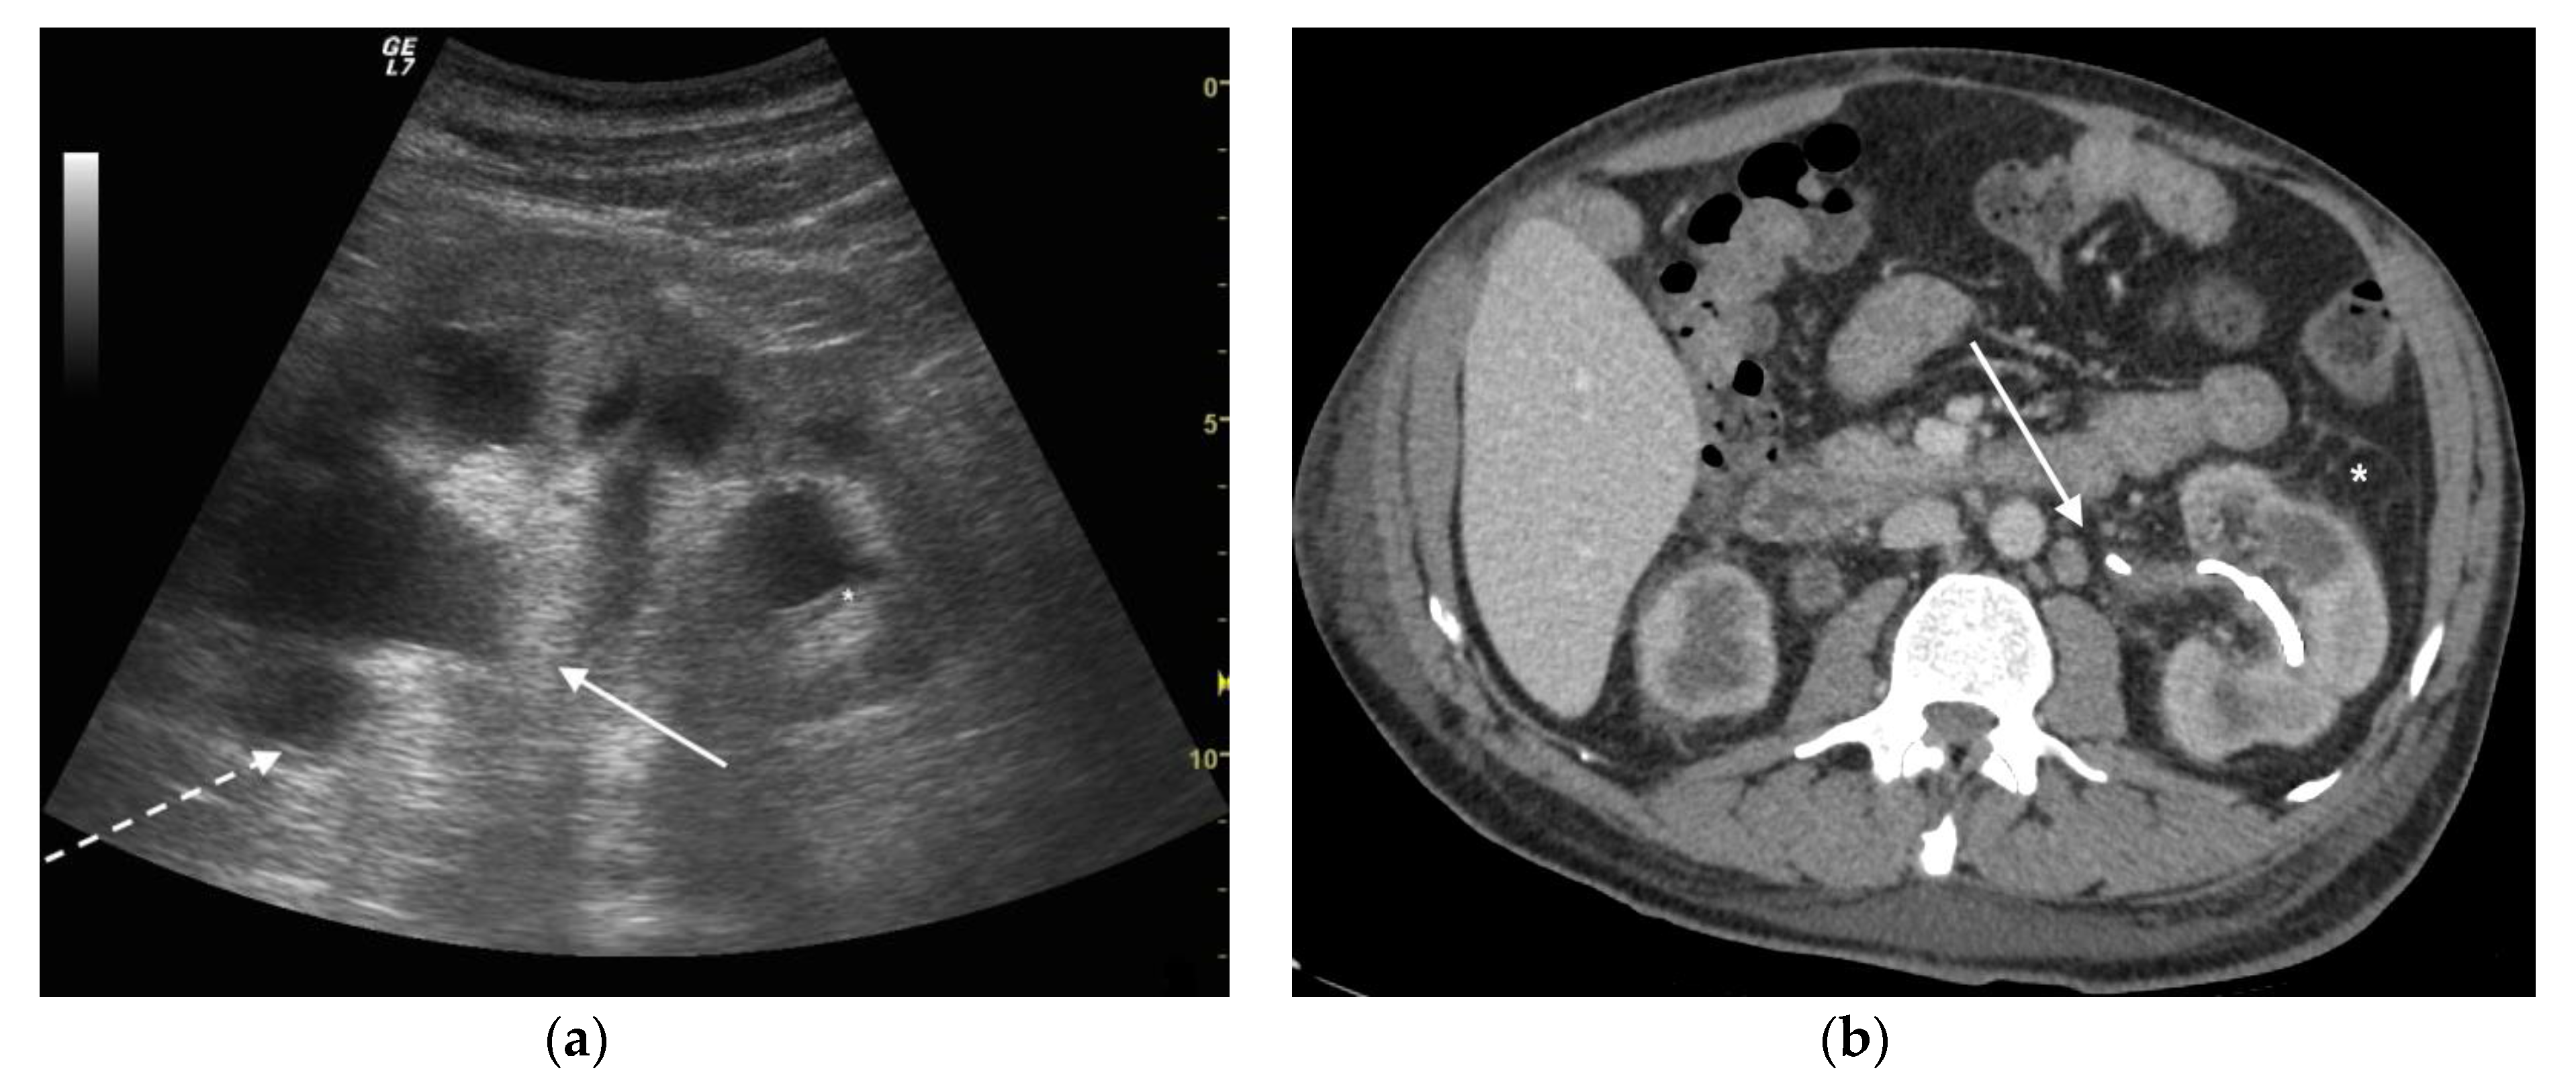

2. MeSH Terms

4. CT